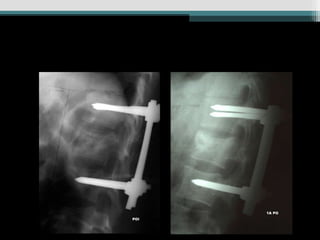

Caso 1 (34anos, queda, Fk e)